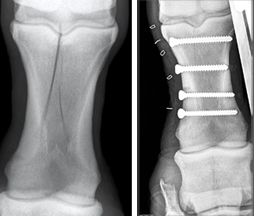

Above are before-and-after views of the right foreleg of a horse that sustained a hairline pastern-bone fracture in Olympic cross-country competition. Jack Snyder, DVM, PhD, Dipl. ACVS, and another doctor made the repair with four compression screws.

"Yes, Jack and Dr. Cedric Chan performed the surgery at the Hong Kong Jockey Club. The horse is doing well and should fly back to his home country at the end of the games. It sustained a spiral P1 fracture, which was repaired with four compression screws," Snyder's wife, Sharon J. Spier, DVM, PhD, Dipl. ACVIM, tells DVM Newsmagazine in an e-mailed news update Wednesday from the equestrian venue in Hong Kong, 1,200 miles south of the main Olympics competition in Beijing.